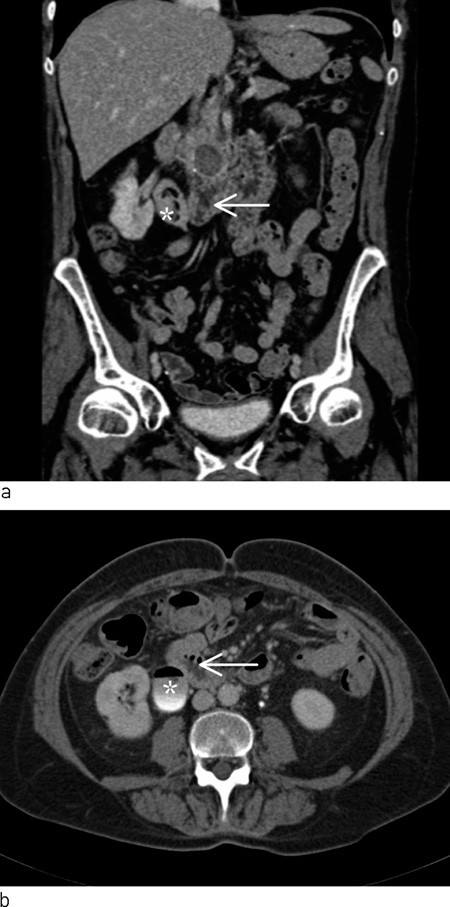

Pasienten ble undersøkt på urologisk poliklinikk tre uker senere. Orienterende blodprøver viste hemoglobin 13,0 g/dl (11,7 – 15,3 g/dl), CRP 3 mg/l (< 10 mg/l), karbamid 9,0  mmol/l (3,0 – 6,5 mmol/l), kreatinin 81 μmol/l (50 – 90 μmol/l). Glukose ble ikke tatt. Ved cystoskopi ble det funnet rikelig med grumsete urin i urinblæren. Det ble ikke påvist konkrementer eller andre fremmedlegemer, og det var ingen patologi i blæreslimhinnen. Cytologi av urin viste normale celler uten atypi. Det ble rekvirert CT urinveier for å undersøke om pasientens hematuri kunne skyldes konkrementer eller prosesser i øvre urinveier eller i relasjon til urinveiene. To uker senere ble det utført CT nyrer og urinveier uten røntgenkontrast og med røntgenkontrast i to faser som viste rikelig med gass i urinblæren og i samlesystemet på høyre side. På høyre side hadde pasienten markert nyrebekken med enkelte fylningsdefekter. Calyces og ureter var slanke. Duodenum lå nært det markerte nyrebekkenet. Venstre nyre og ureter var upåfallende. I caput pancreatis ble det påvist forkalkninger og en cyste med diameter 1,5 cm (fig 1).

Pasienten kom tilbake til Norge fem måneder etter at hun ble utskrevet fra avdelingen, og det ble gjort CT urinveier som viste uendrede forhold i urinveiene med gass i høyre nyres samlesystem og i urinblæren. I høyre nyrebekken ble det funnet fylningsdefekter som ble oppfattet som debris eller koagler. Cysten som tidligere var sett i pancreas var økt til 2,5 cm i diameter og hadde litt økt tetthet. Hun ble innkalt til ny poliklinisk kontroll. Dyrkning av urin viste tre ulike ikke navngitte mikrober, tolket som forurensning.

Pasienten reiste igjen til utlandet, og utredningen ble utsatt. Man valgte å rekvirere ny CT av urinveier før planlagt fleksibel ureterorenoskopi. Gjentatt CT-undersøkelse av urinveiene med røntgenkontrast i utskillingsfase både i rygg- og bukleie knapt ti måneder etter at hun ble henvist første gang viste uendret gass i urinveiene. Som tidligere lå høyre nyrebekken svært nær duodenum, og på tross av at det ikke var overgang av røntgenkontrast fra urinveier til tarm konkluderte beskrivende radiolog med at det trolig var en fistel mellom nyrebekkenet på høyre side og duodenum. Ved regranskning ble dette funnet oppfattet som usikkert.